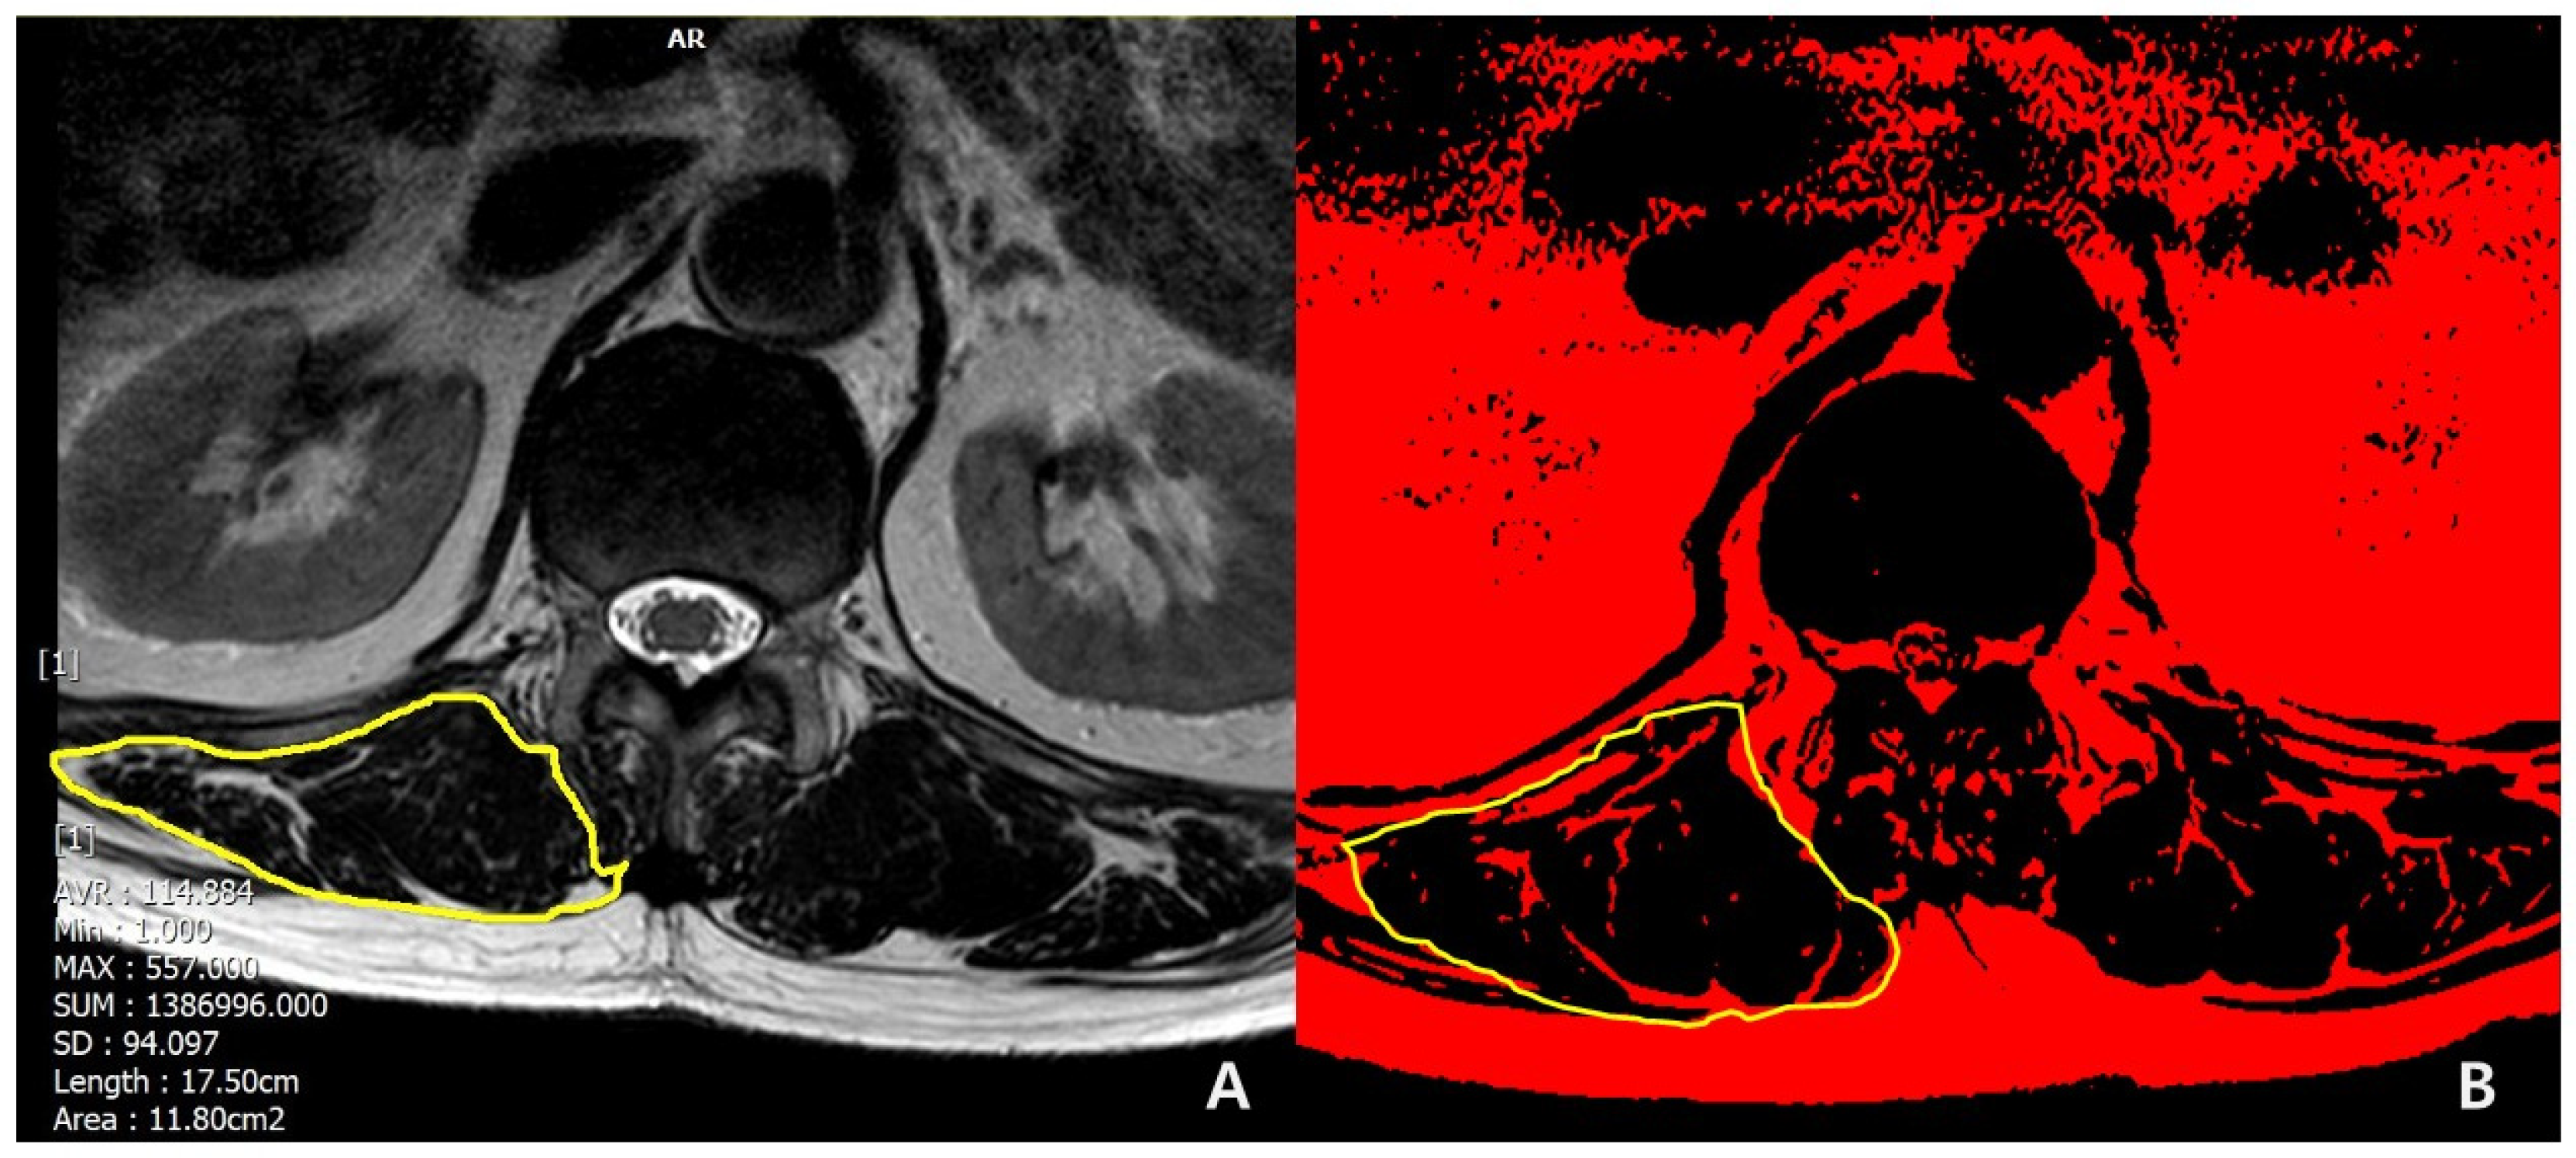

The following demographic and surgical data were collected: age at surgery; sex (female/male); bone mineral density (BMD, T-score); body mass index (BMI, kg/m2); smoking; previous spinal fusion; American Society of Anesthesiologist physical status (ASA) grading; iliac fixation; disc degeneration by Pfirrmann grade [16] at T12-L1 segment (1,2,3: mild to moderate; 4,5: severe); muscularity status at T12-L1 (cross-sectional area [CSA], cm2); and fat infiltration grade (mild to moderate, if <50%; severe, if ≥50%) in erector spinae muscle at T12-L1 in T2-weighted axial magnetic resonance (MR) images using Picture Archiving and Communication System (PACS) by Philips ACHIEVA 3.0T (Philips Healthcare, West Sussex, UK) and the ImageJ for windows (National Institutes of Health, Bethesda, MD, USA, V 1.8.0). The region of interest (ROI) for erector spinae muscle at the T12-L1 level was outlined polygonally with the manipulation of a graphic cursor and was handled with the pseudocoloring method [17] (Figure 2). Then, CSAs (Figure 2A) were calculated, and the fat infiltration grade (Figure 2B) was determined.

Figure 2.

Methods for measuring (A) CSA and (B) FI of erector spinae muscle.